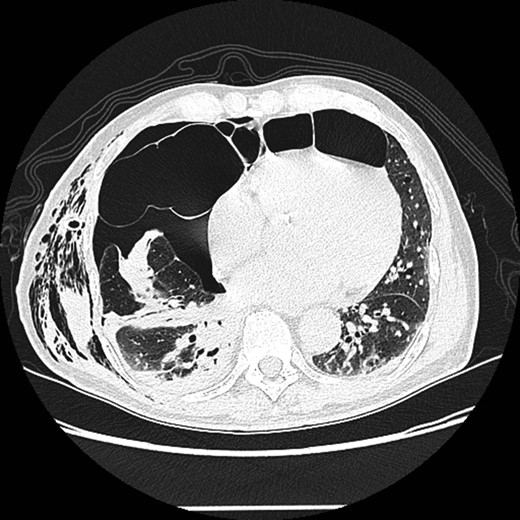

A 73-year-old male patient with a clinical history of COPD, lung emphysema and a 30-year smoking history was admitted to the ED due to a 24-h clinical picture of dyspnea immediately following a sudden bout of dry coughing. Physical examination showed a dyspneic patient, tachypnea of 25 rpm, heart rate of 85 bpm and blood Pressure of 135/75 mmHg along with central cyanosis. Chest exam showed a hyper-resonant right hemithorax along with reduced breath sounds. Initial chest X-ray revealed a large right-sided pneumothorax (Fig. 1). A right chest tube was placed in the ED. Emergency echocardiogram had no significant findings and spirometry showed suspected patterns of obstruction. Following patient stabilization, a high-resolution chest computed tomography (HRCT) was performed revealing extensive pan lobar emphysema throughout both lungs, para septal emphysema in both the anterior upper lobes and herniation of a left lung bullae through the anterior mediastinal pleura along with a right-sided pneumothorax with the chest tube in place with persistent air space (Fig. 2). The patient was taken to surgery where a right video-assisted thoracoscopic (VATS) approach showed severe lung emphysema and a contralateral herniated left lung bulla through the mediastinal pleura anterior to the pericardium (Fig. 3). Right pleurodesis was performed using Talc and a left posterior thoracoscopy showed a severe emphysematous left lung with a lingular herniated bulla to the right hemithorax through an anterior mediastinal pleural defect along with pleural adhesions (Figs 4 and 5). Thoracoscopic hernia reduction was performed along with bullectomy using 60 mm mechanical sutures (Fig. 6). Chest tubes were removed on POD 3 (right) and POD 4 (left). The patient had significant respiratory improvement and was discharged on POD 5.

High-resolution computed tomography (HRCT) thorax showing trans‐mediastinal herniation of pulmonary bulla with right pneumothorax.